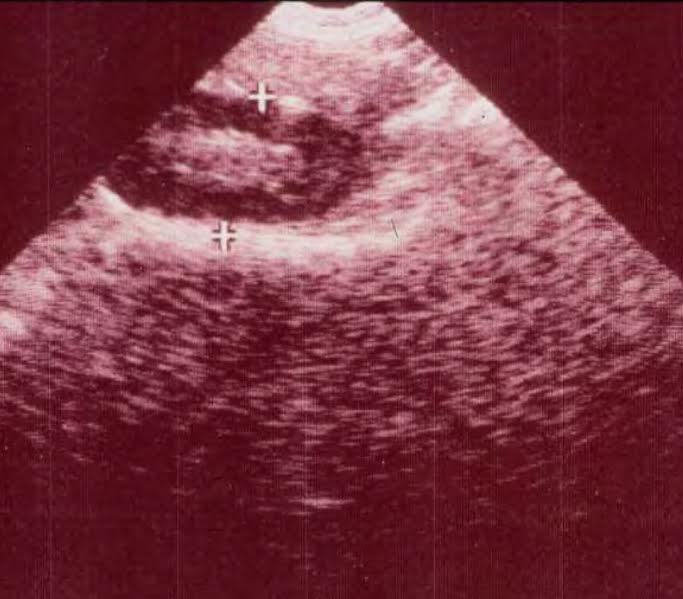

What segment of the intestinal tract is visualized on this picture?

Pelvic flexure

What is the Dx on this foal?

A) lipoma

B) anterior enteritis

C) adhesions

D) intussusception

E) herniation through the mesenteric rent